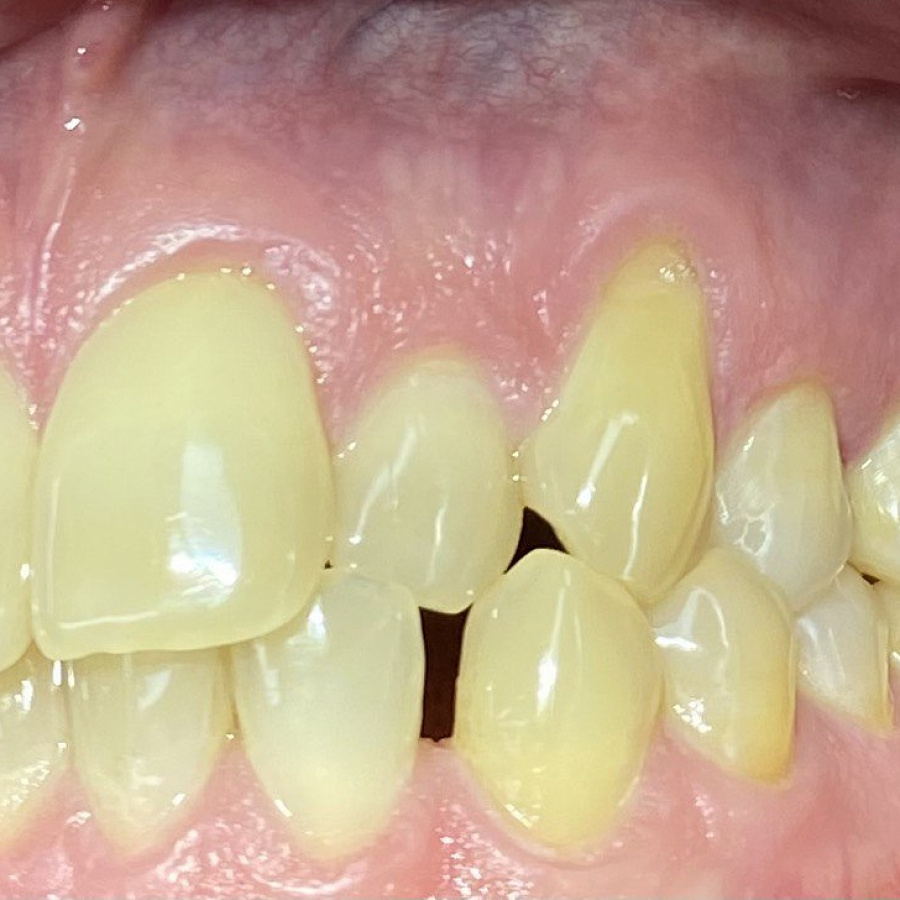

Пациент обратился с жалобами на неровные передние зубы верхней и нижней челюстей.

Диагностика показала:

• сужение зубных рядов,

• обратное перекрытие в области фронтальных зубов слева,

• разворот по оси передних зубов верхней и нижней челюстей,

• стираемость эмали зубов,

• индивидуальную микродентию 12 и 22 зубов.